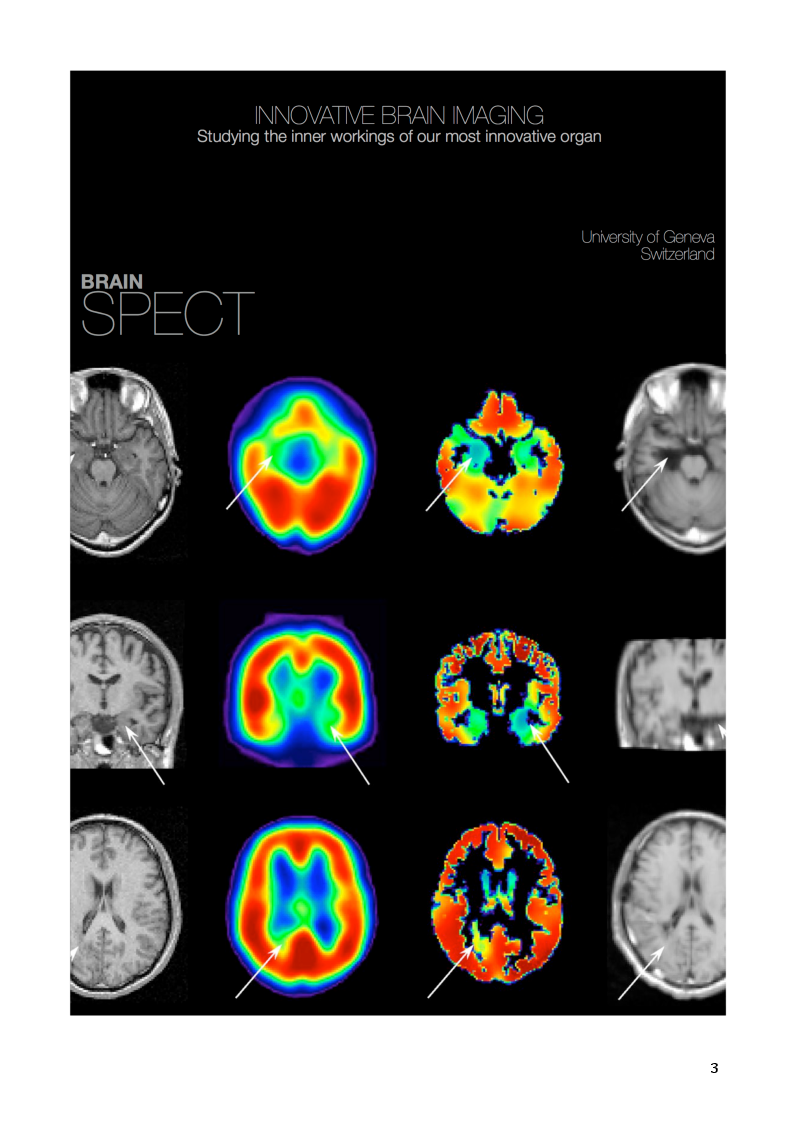

Comparison of [123I]Epidepride & [123I]IBZM SPECT tracers for Brain Dopamine D2 Receptor Imaging using Micro SPECT

The importance of this thesis is to quantitatively compare two widely used SPECT radiotracers [123I]IBZM - Iodobenzamide: [123I](S)-2-hydroxy-3-iodo-6-methoxy- (1-ethyl-2-pyrrolidinylmethyl)-benzamide and [123I]Epidepride: [123I](S)-N -((1- ethyl-2-pyrrolidinyl) methyl)-5-iodo-2, 3-dimethoxybenzamide in rodents for the first time, both D2 dopamine antagonists and potential imaging agents used in diagnosing various dopamine receptor dependent neurological and psychiatric disorders. The origin of these substituted benzamides comes from atypical anti psychotic agents. Both [123I]Epidepride and [123I]IBZM are benzamine derivatives with very high affinity for dopamine receptors, which in its labelled form can be used as a SPECT tracer. These SPECT tracers can be used to study alterations in D2/D3 levels in specific brain regions. Significance of alternations of dopamine D2/D3 receptor conditions were widely substantiated in Schizophrenia, Parkinson’s, Restless leg syndrome etc. (Kessler RM 1991, Al-Tikriti MS 1994)

The purpose of this study was to evaluate the bio distribution and pharmacokinetics of [123I]IBZM and [123I]Epidepride brain SPECT. Even though [123I]IBZM is widely preferred as a D2 receptor-imaging agent, distinctive image standards are stipulated by a relatively low target-to-non target ratio (Olsson H 2001). In Vitro and In vivo animal studies suggest that [123I]Epidepride may be preferred to [123I]IBZM (Kessler RM 1992, Al-Tikriti MS 1994, Scherfler C 2005). This study has shown a systematic comparison of both tracers in rodents by comparing the binding potentials obtained from raw VOI images and pixel wise comparison and proposed new insights about Epidepride kinetics which are currently unaccounted.

Our results comply with previously reported data and show that iodobenzamide – [123I]IBZM has a moderate putamen to cerebellum ratio in rodent brain and less binding potential compared with [123I]Epidepride in striatal regions and extra striatal regions. [123I]Epidepride showed its ability to identify extra striatal regions in the following order, Mid Brain >Temporal Cortex > Frontal > Occipital > Cerebellum and showed its exceptional properties. Thus [123I]Epidepride is superior to [123I]IBZM and shows excellent imaging characteristics of both striatal and extra striatal dopamine D2 receptors (Pinborg 2007). Absolutely [123I]Epidepride is superior to [123I]IBZM but activity from cerebellum cannot be considered as a free and non- specifically bound radio ligand while using reference tissue models with [123I] Epidepride SPECT, therefore finding ways to diminish this will be of appropriate interest.